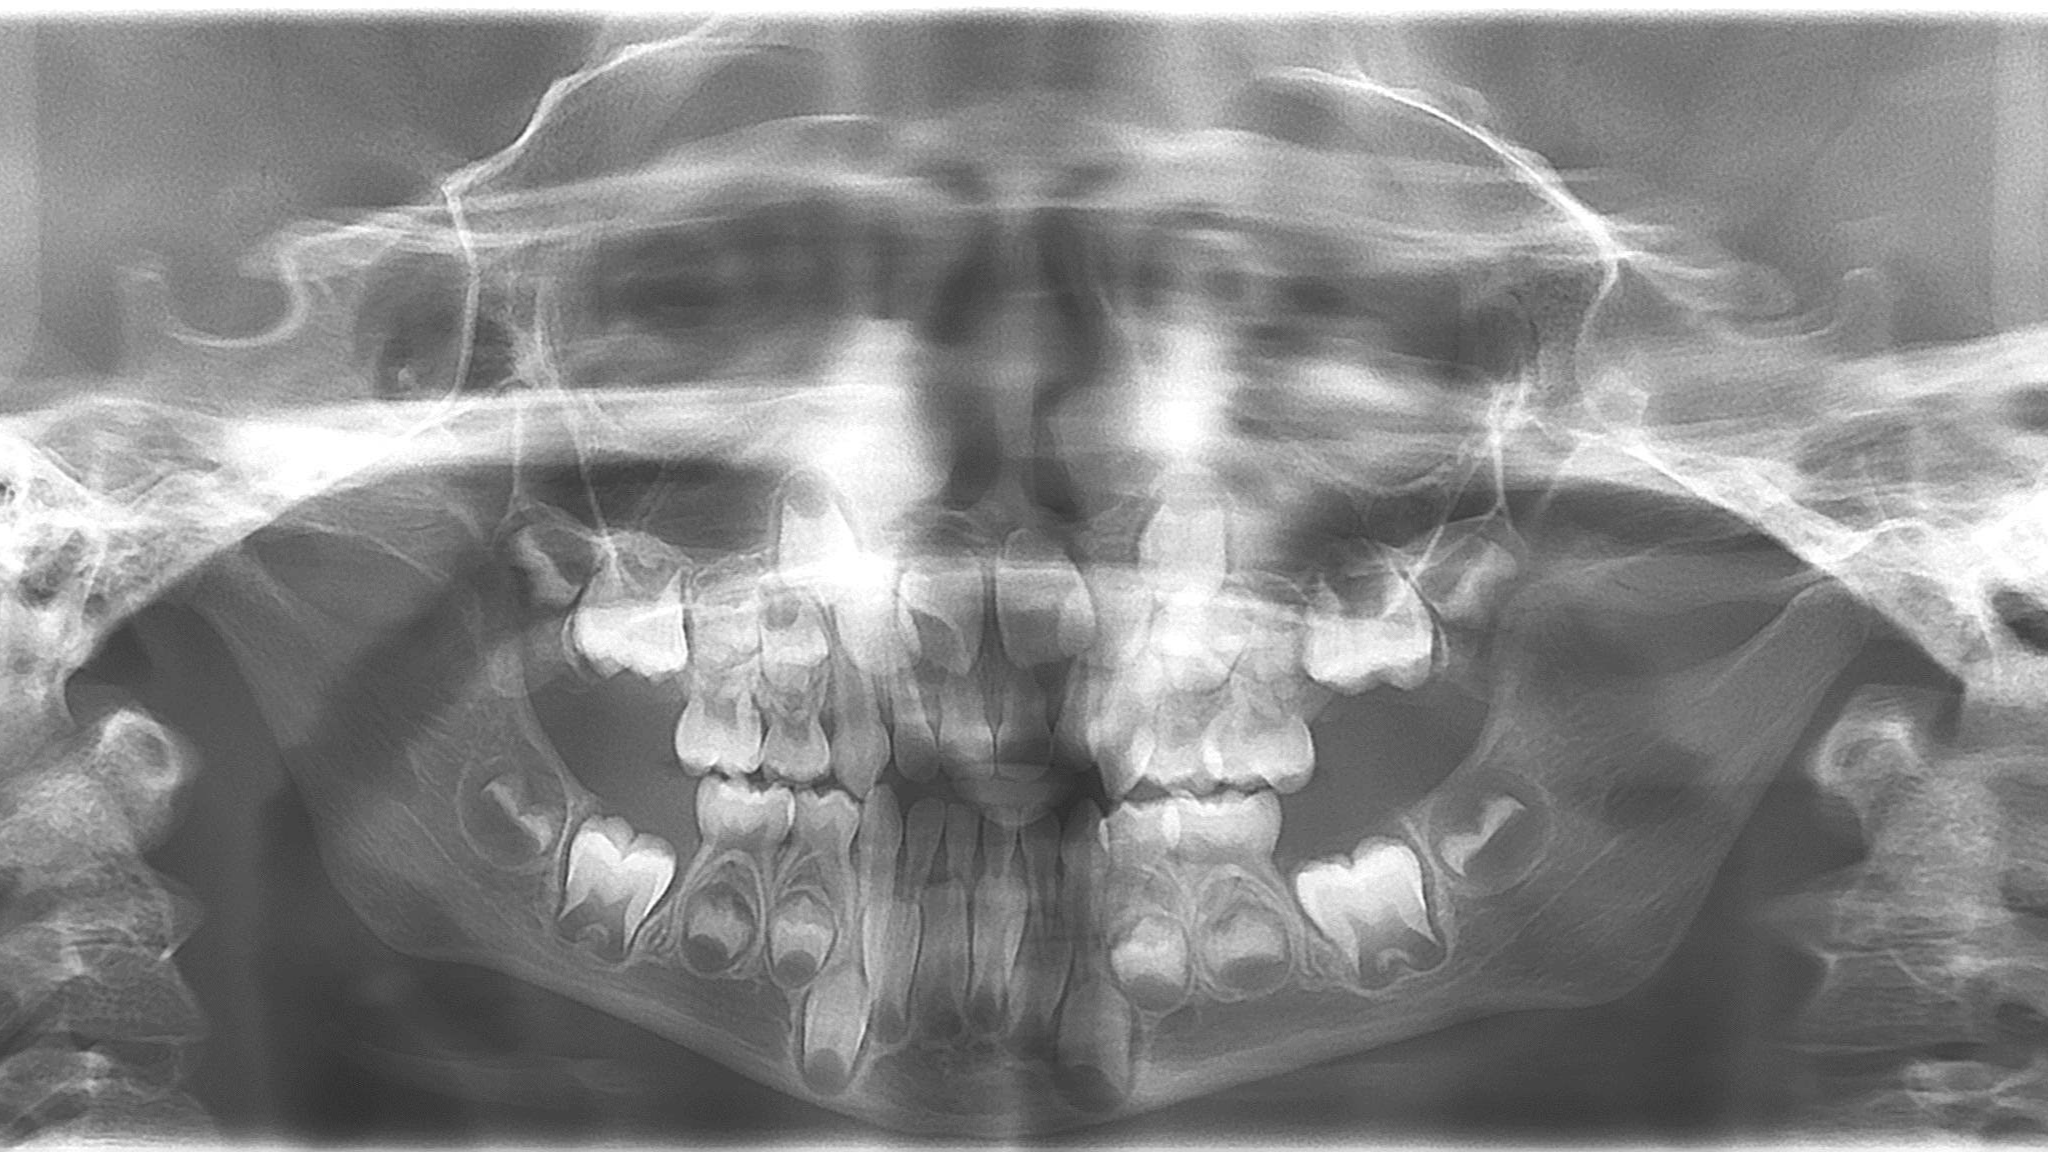

bilan des radiographies début et en cours de traitement